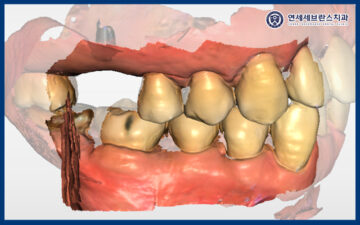

25.12.02

<임플란트 수치 측정 및 보철 작업 시작>

이렇게 약 4개월간의 치유기간을 거친 뒤,

곡반정동임플란트의 수치를 측정해 보니

처음과 다르게 높은 수치로

안정적인 상태를 확인할 수 있었습니다.

그래서 보철 단계로 넘어가

구강 스캐너를 이용해

치아 형태를 정밀하게 촬영하고,

환자분께 자연스럽고 편안하게 맞는

보철물을 제작하기로 했습니다.